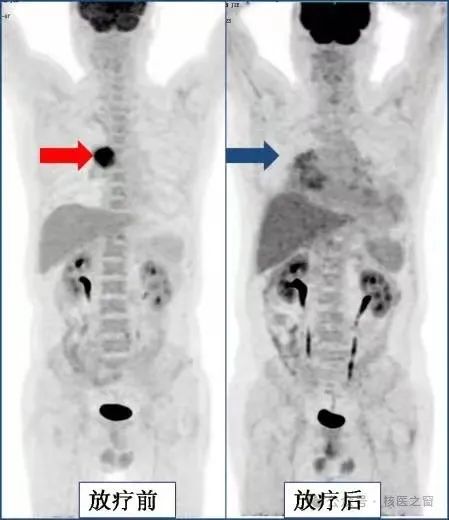

3、评估治疗效果

肺癌放疗后,肿瘤消失,出现放射性肺炎。

淋巴瘤化疗后病灶完全消失。